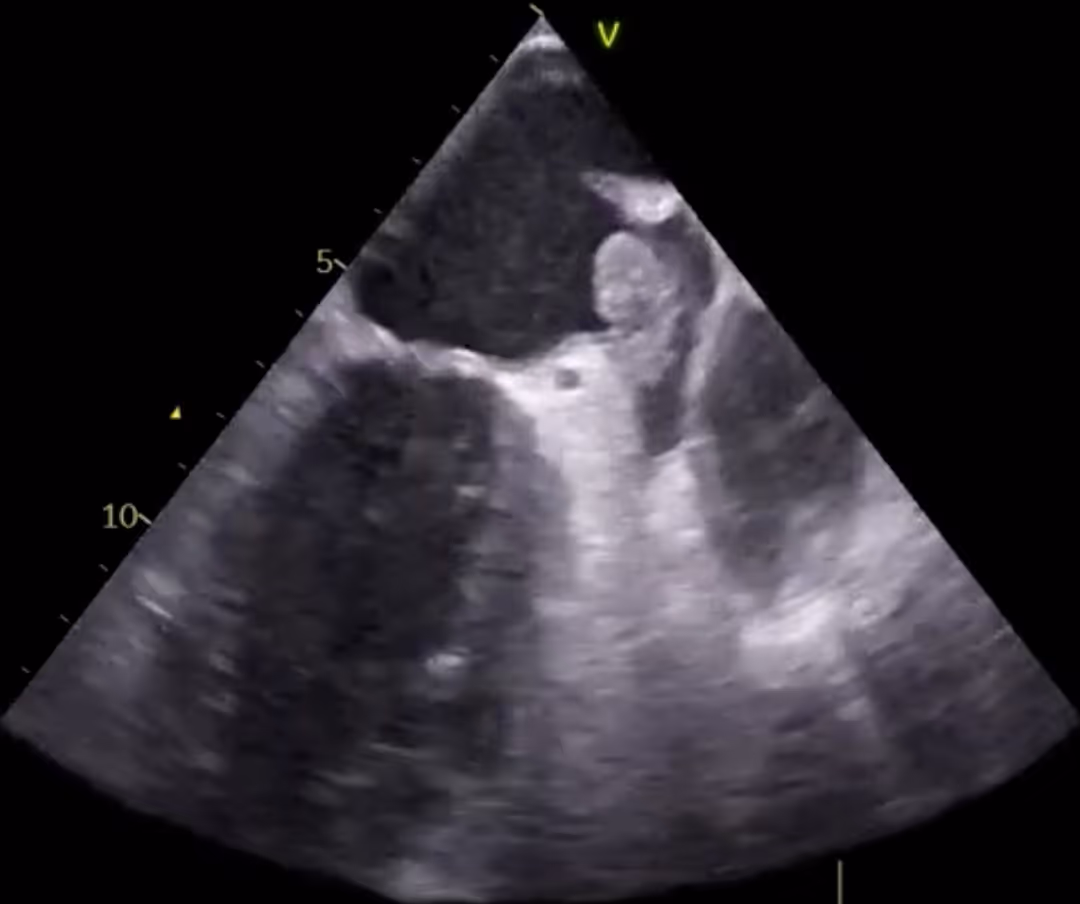

Ventricular septal rupture as a complication of subacute myocardial infarction

2021-02-01

in

Clinical Cases